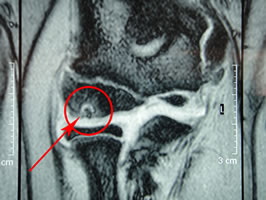

最後にMRI画像です。

T2強調画像(↓)

T1・T2いずれも赤矢印先に丸くポツンと描出されているのが患部です。

最後の画像(↓)はMRI T1での短軸(横向き)です。

やはり赤矢印の先に、離断性骨軟骨炎が描出されています。